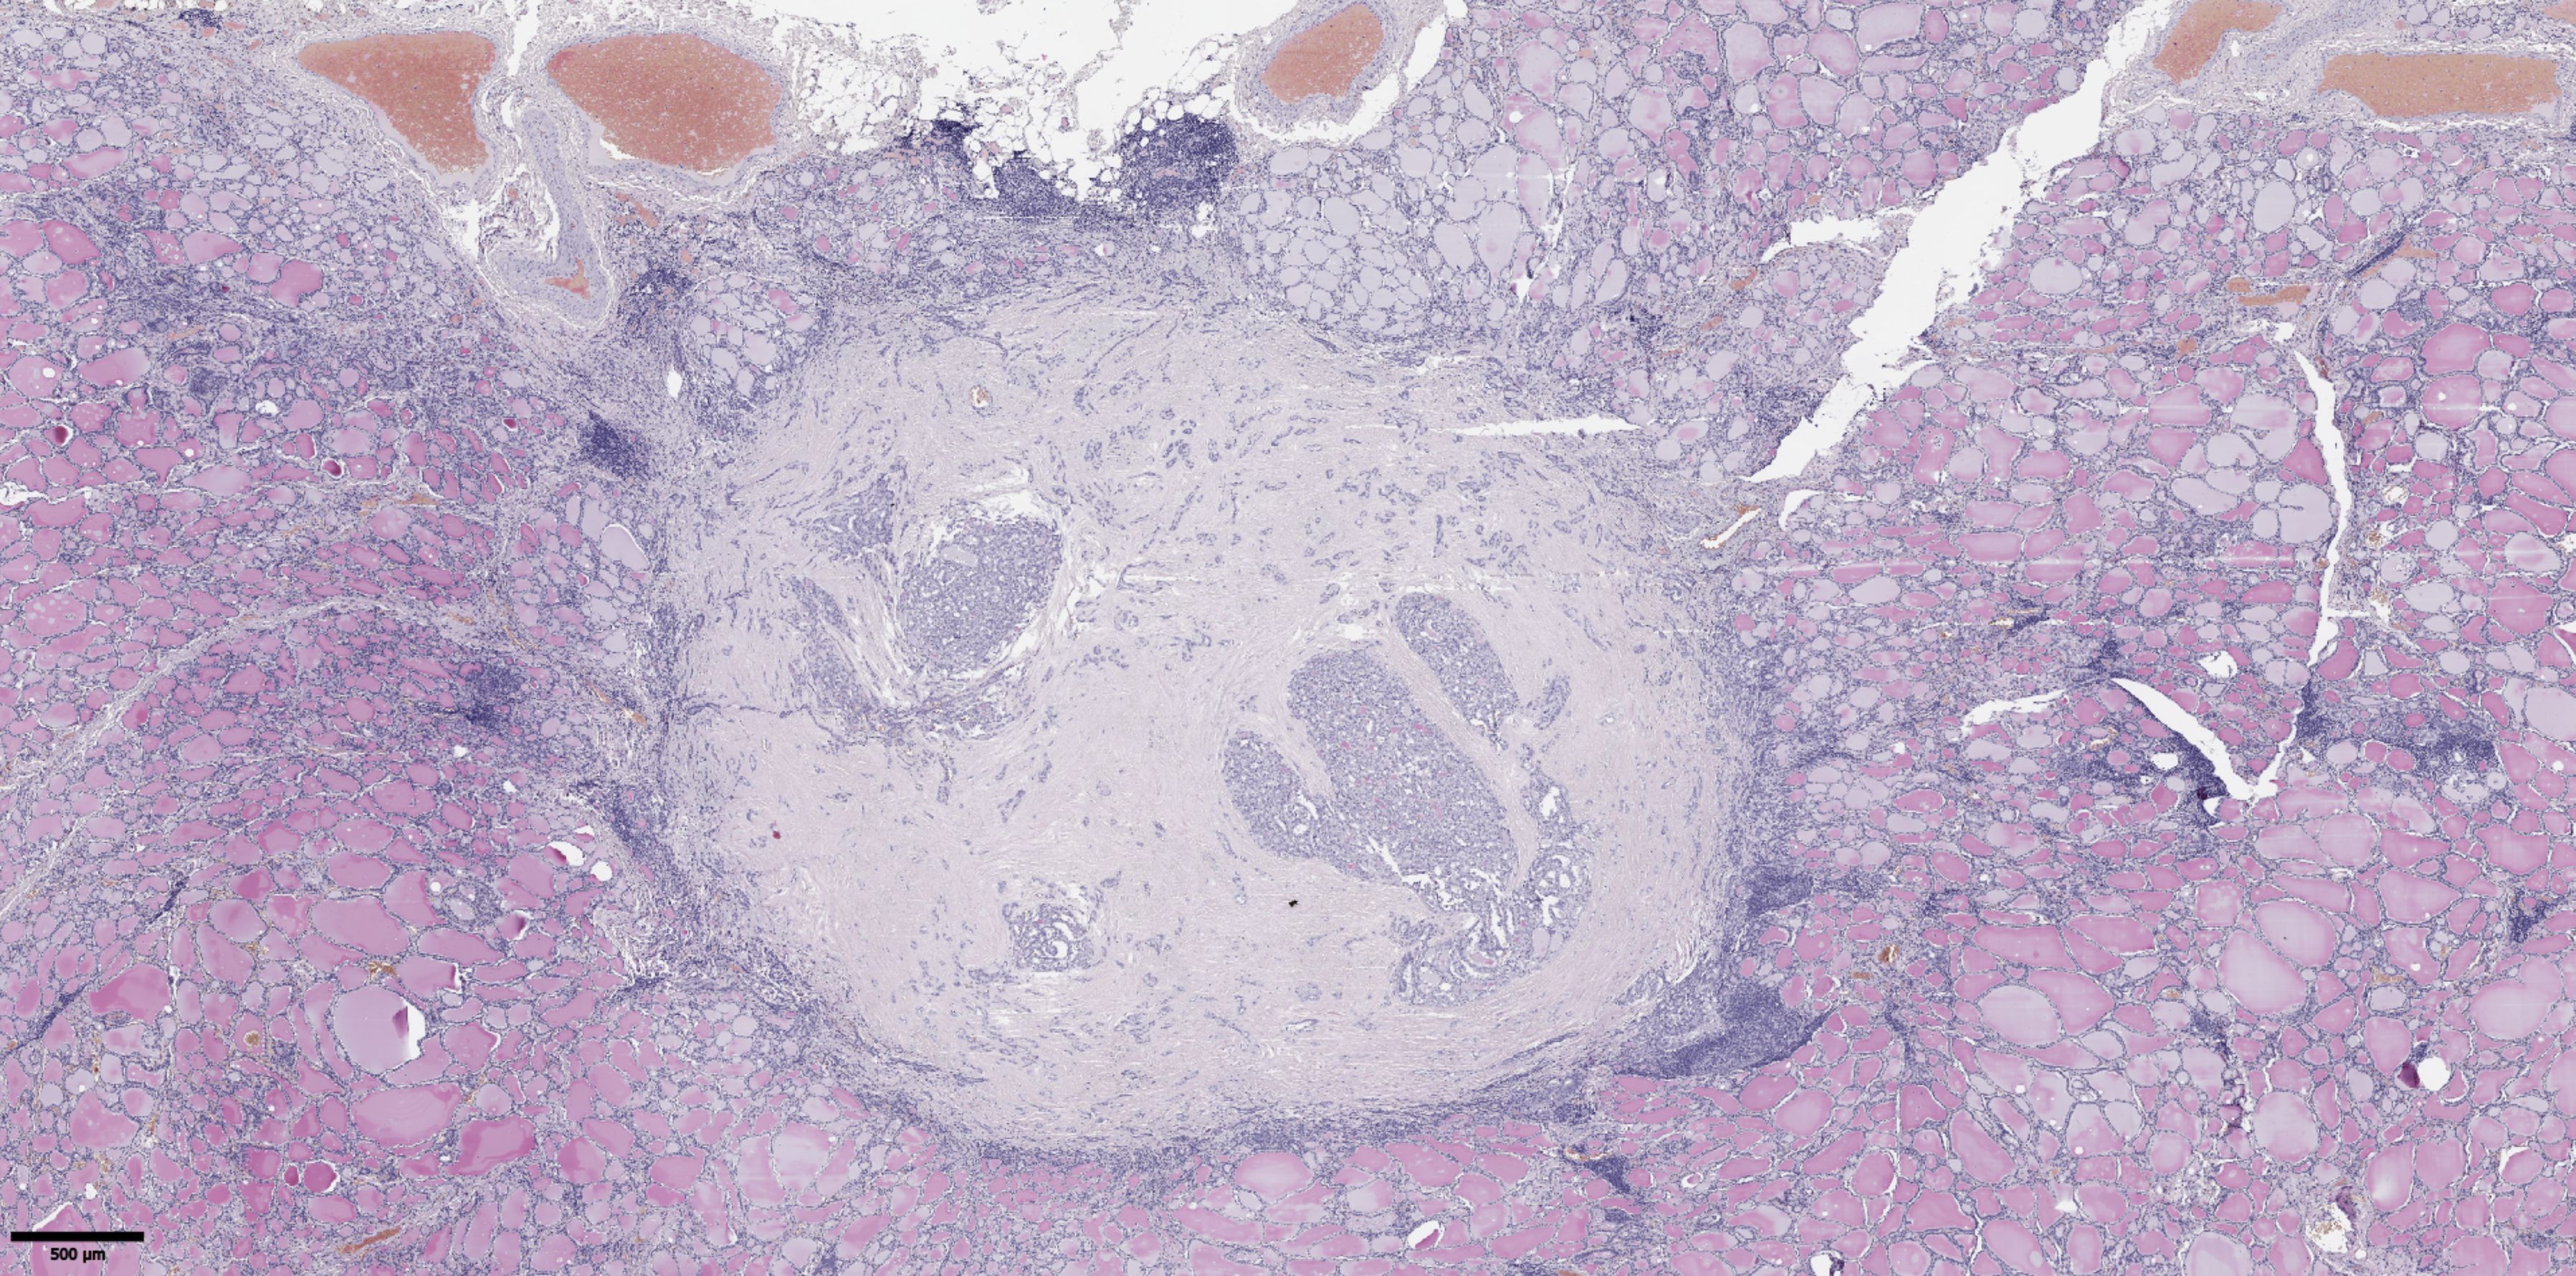

The groups were compared based on a number of tumor morphological features. The following were evaluated: the largest tumor node (Figure 1) and metastatic focus size (Figure 2), the histological subtype of papillary carcinoma according to the WHO classification (26), the presence of tall cell (Figure 3), Warthin-like, and squamous cell components in the tumor, foci of calcification and ossification in the tumor, a lymphocytic rim around the tumor node in the thyroid lobe tissue, apical vacuoles in tumor complexes, psammoma bodies in the tumor tissue (Figure 4) and in the thyroid tissue outside the tumor, the presence of a tumor capsule or its fragments, tumor “buds” (Figure 5), invasion of adipose tissue, perineural invasion, concomitant nodular thyroid diseases (tumor and non-tumor), and thyroiditis. Additionally, the following nuclear features of tumor cells were noted: angular contours, nuclear grooves, and intranuclear pseudoinclusions (Figure 6). Nucleoli in tumor cell nuclei were assessed using criteria partly adopted from the modified WHO/ISUP classification by S.A. Fuhrman for grading renal cell carcinomas (27), namely: the presence of nucleoli basophilic, visible but not prominent at ×100, or nucleoli conspicuous at ×100, basophilic, or nucleoli conspicuous at ×100, eosinophilic at ×400. Furthermore, the number of mitotic figures per 2 mm² of tumor tissue in “hot spots” and the presence of atypical mitotic figures were assessed. The degree of tumor fibrosis was visually graded as 0 (no fibrosis), 1 (fibrosis in less than 50% of the tumor node), or 2 (fibrosis in 50% or more of the tumor node) (Figure 7). A tumor “bud” was defined as a tumor complex no larger than 0.1 cm in diameter, located no more than 0.1 cm far from the tumor node, with one or more non-neoplastic thyroid follicles between them, which could not be reliably differentiated during routine histological examination between a tumor embolus in a vessel lumen (blood or lymphatic), an additional independent microfocus of tumor growth, or a tangential section of a tumor invasion area into adjacent thyroid tissue.

Figure 7. Histological images of papillary thyroid microcarcinoma with fibrosis in 50% or more of the tumor node. Hematoxylin–eosin, х20.